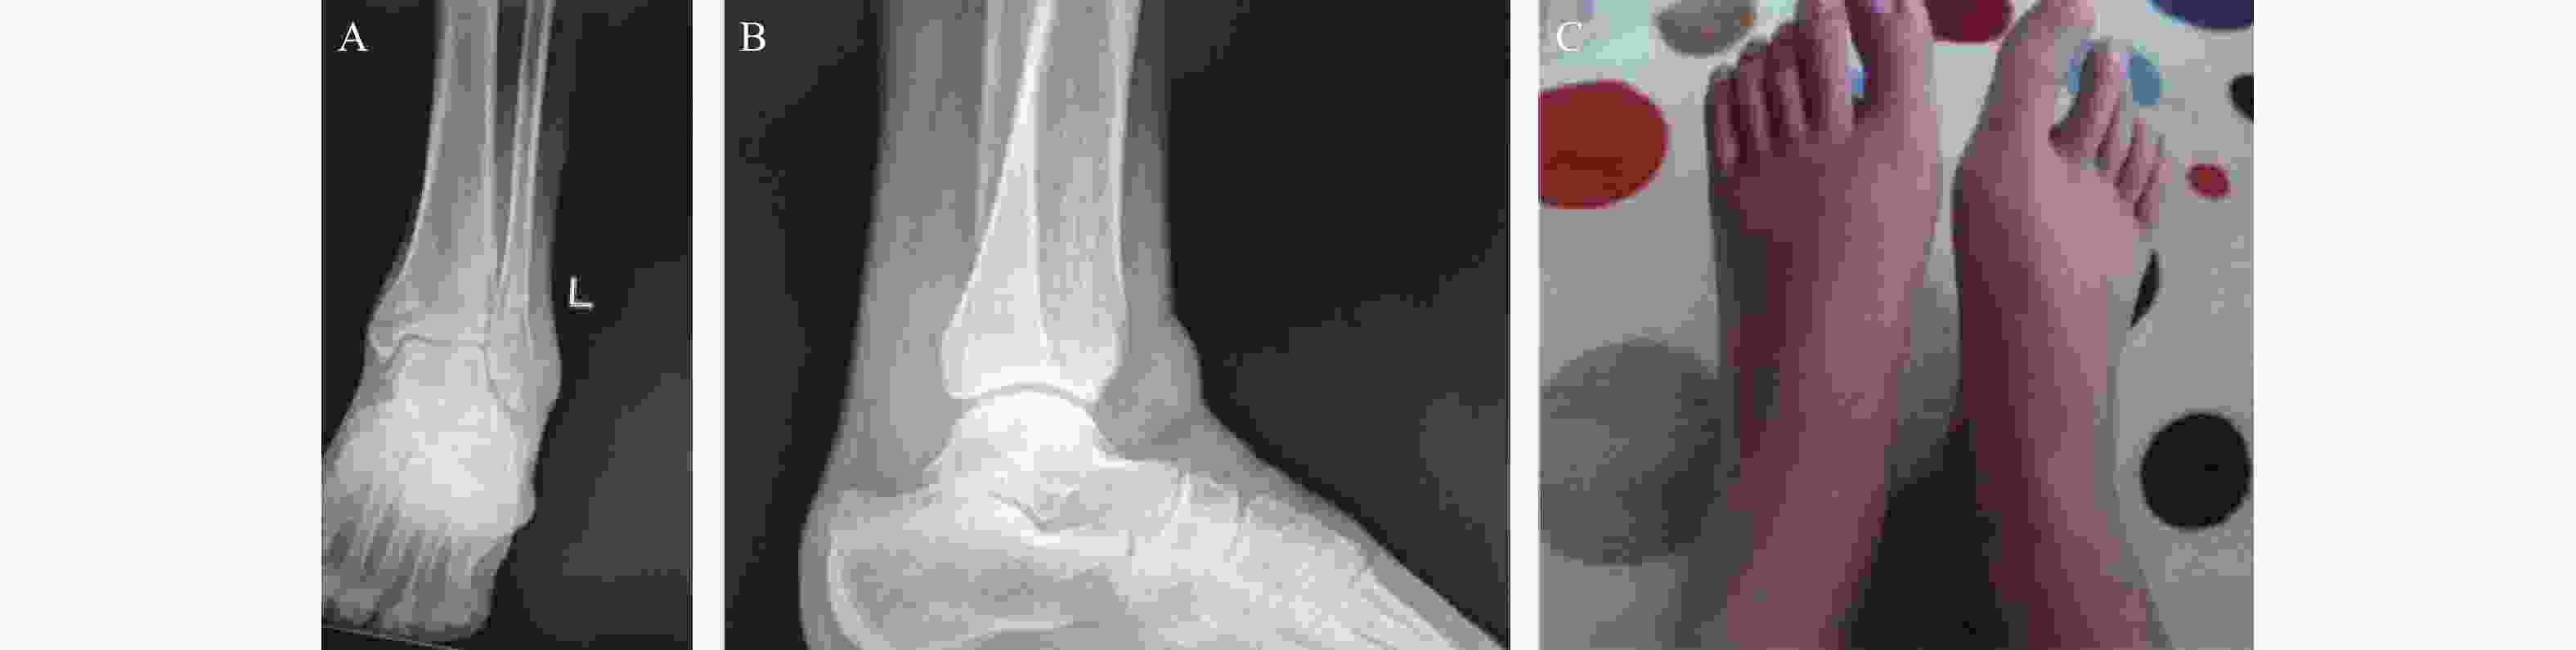

图  2  典型病例

A~B:治疗前患侧踝关节正位、侧位X线片;C:治疗前双足图片。

Figure  2.  Typical case